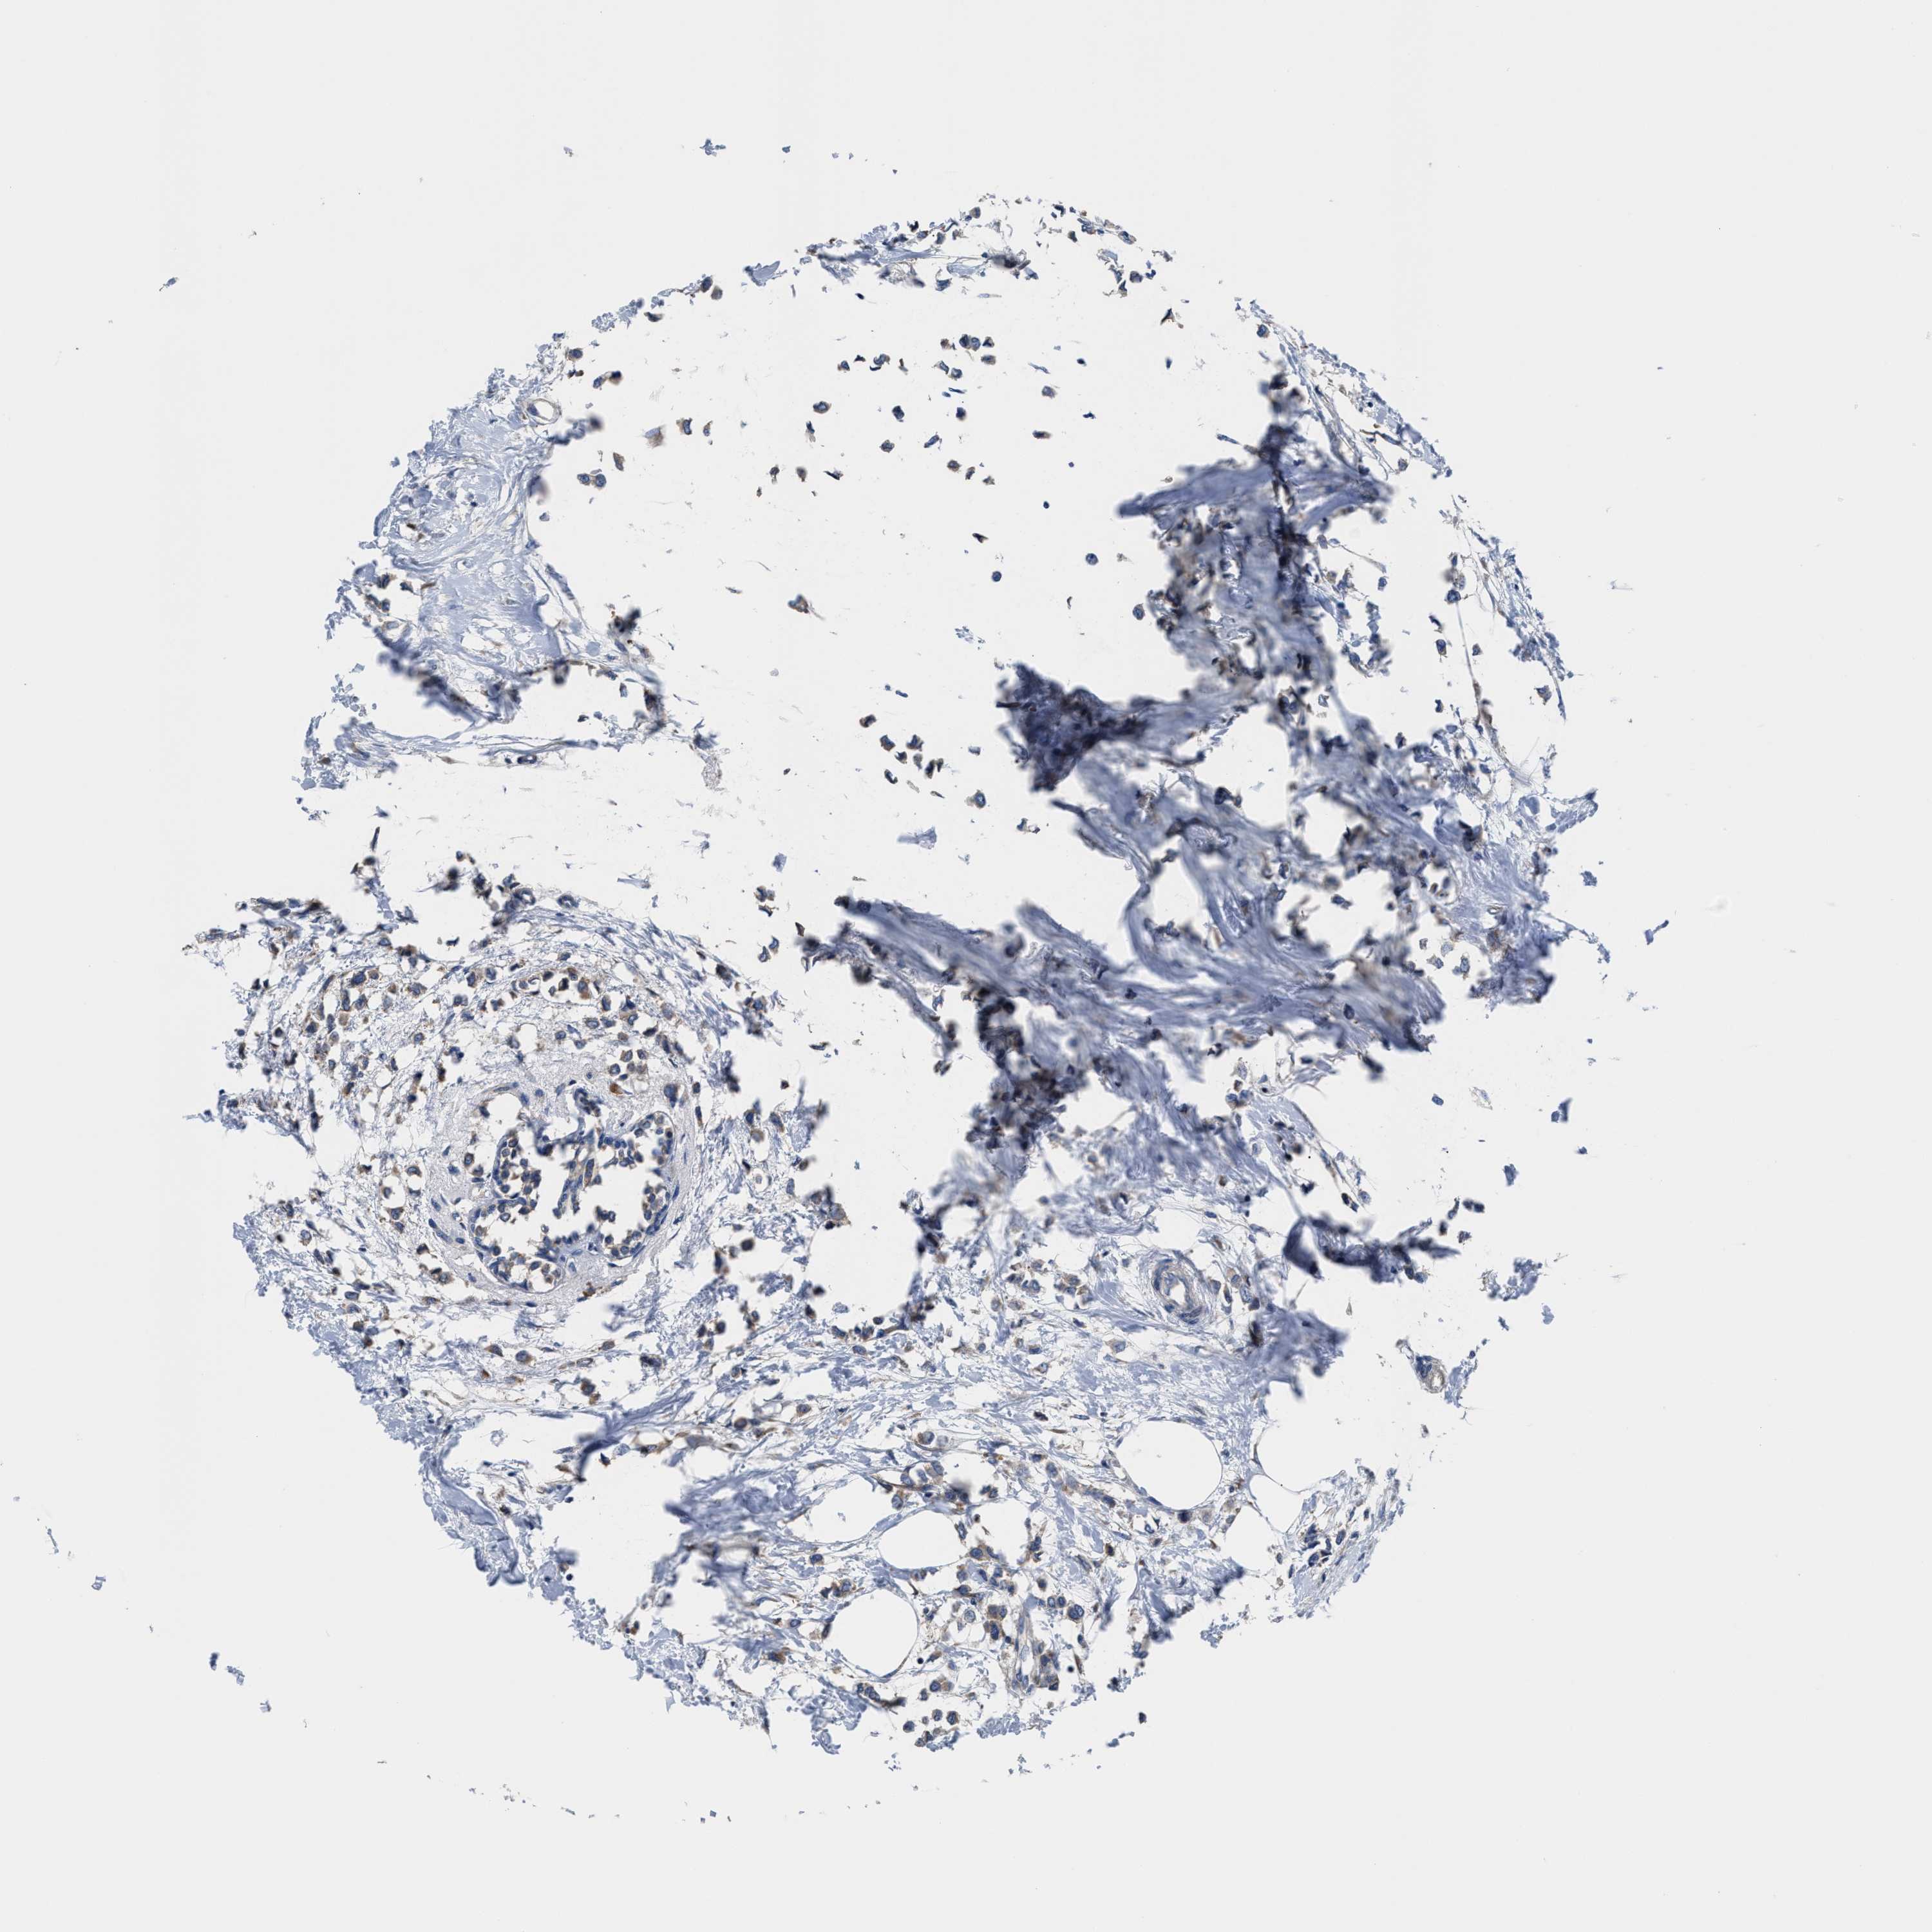

BRCA TCGA BRCA VALIDATION PROTEIN EXPRESSION